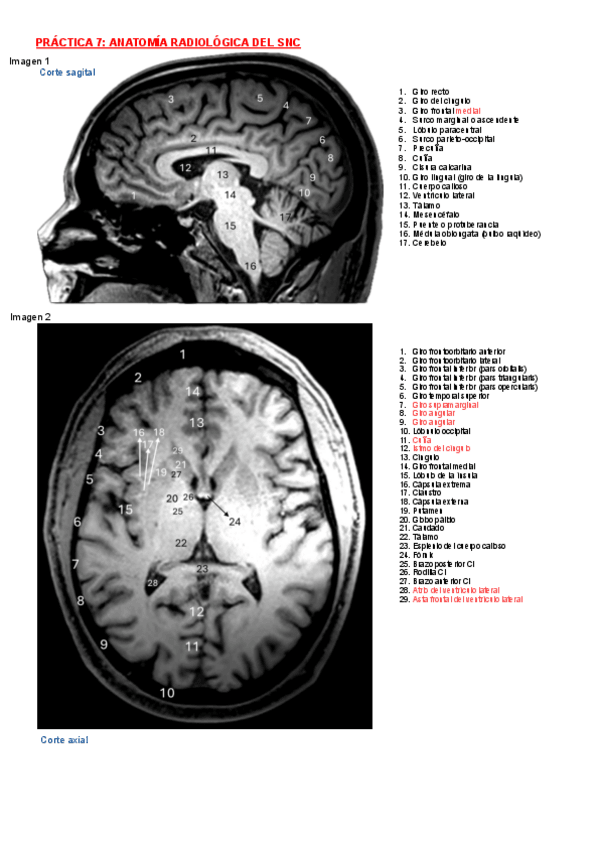

He publicado nuevos apuntes de 2º Anatomía Humana Iii: Modelos-Practicas.pdf

26 páginas